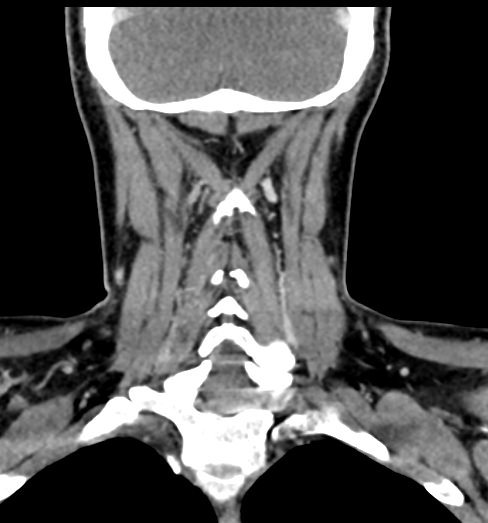

Мультиспиральная компьютерная томография – это высокоинформативный лучевой метод диагностики различной патологии мягких тканей шеи, включая воспалительные заболевания, травматические повреждения и опухолевые процессы. КТ позволяет оценить состояние щитовидной железы, паращитовидных желез, гортани, верхней части пищевода, магистральных сосудов шеи, шейных лимфоузлов и окружающих мягких тканей.

Метод КТ основан на применении рентгеновского излучения. Однако в отличие от обычного рентгена, при котором снимки производятся в одной плоскости, при КТ излучатель рентгеновских лучей постоянно двигается вокруг объекта исследования, проводя сканирование в различных плоскостях, а затем трансформируя полученные данные в цифровые трехмерные изображения. Это дает возможность визуализировать органы и ткани в мельчайших подробностях, а с помощью объемных 3D-реконструкций наглядно оценить пространственное расположение органов и патологических образований.

Рентгеновские лучи лучше всего поглощаются плотными структурами, такими как костная ткань. Поэтому кости хорошо видны на снимках КТ. Это делает компьютерную томографию незаменимой при необходимости обследования, в частности, костного скелета гортани. Однако для улучшения визуализации мягких тканей требуется введение специального контрастного препарата, поэтому КТ мягких тканей шеи проводится с контрастным усилением.

Для контрастирования используется йодсодержащее контрастное вещество, которое в составе рентгеноконтрастного препарата вводится в вену пациенту непосредственно во время исследования. Благодаря способности контраста поглощать рентгеновские лучи на снимках КТ хорошо контрастируются кровеносные сосуды и опухолевые образования, имеющие, как правило, развитую сосудистую сеть. Методика внутривенного болюсного контрастирования помогает обнаружить воспалительные изменения, отличить доброкачественные опухоли от злокачественных, выявить поражение лимфатических узлов и степень прорастания опухоли в магистральные сосуды и окружающие ткани.